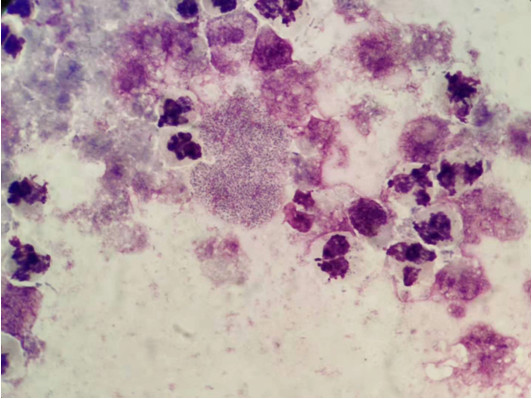

图1 (标本培养前涂片,显微镜×100瑞氏染色)

忙碌的下午准备下班之际,感染科送来了一份胸水标本,外观乳白色、浑浊糊状、脓性,我按部就班做好一般细菌培养和胸水常规,并推两张片分别进行瑞氏染色和革兰染色,待干后镜检。革兰染色片找到大量白细胞、细小革兰阳性球菌和少量革兰阴性杆菌,同时存在中性粒细胞吞噬细菌的情况。瑞氏染色找到大量白细胞、成团细小球状菌及少量杆状菌,细胞手工分类:中性粒细胞99%,淋巴细胞1%,镜检后报告临床医生找到革兰阳性球菌和革兰阴性杆菌以及细胞分类结果。